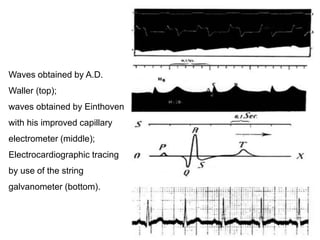

Waves obtained by A.D.

Waller (top);

waves obtained by Einthoven

with his improved capillary

electrometer (middle);

Electrocardiographic tracing

by use of the string

galvanometer (bottom).